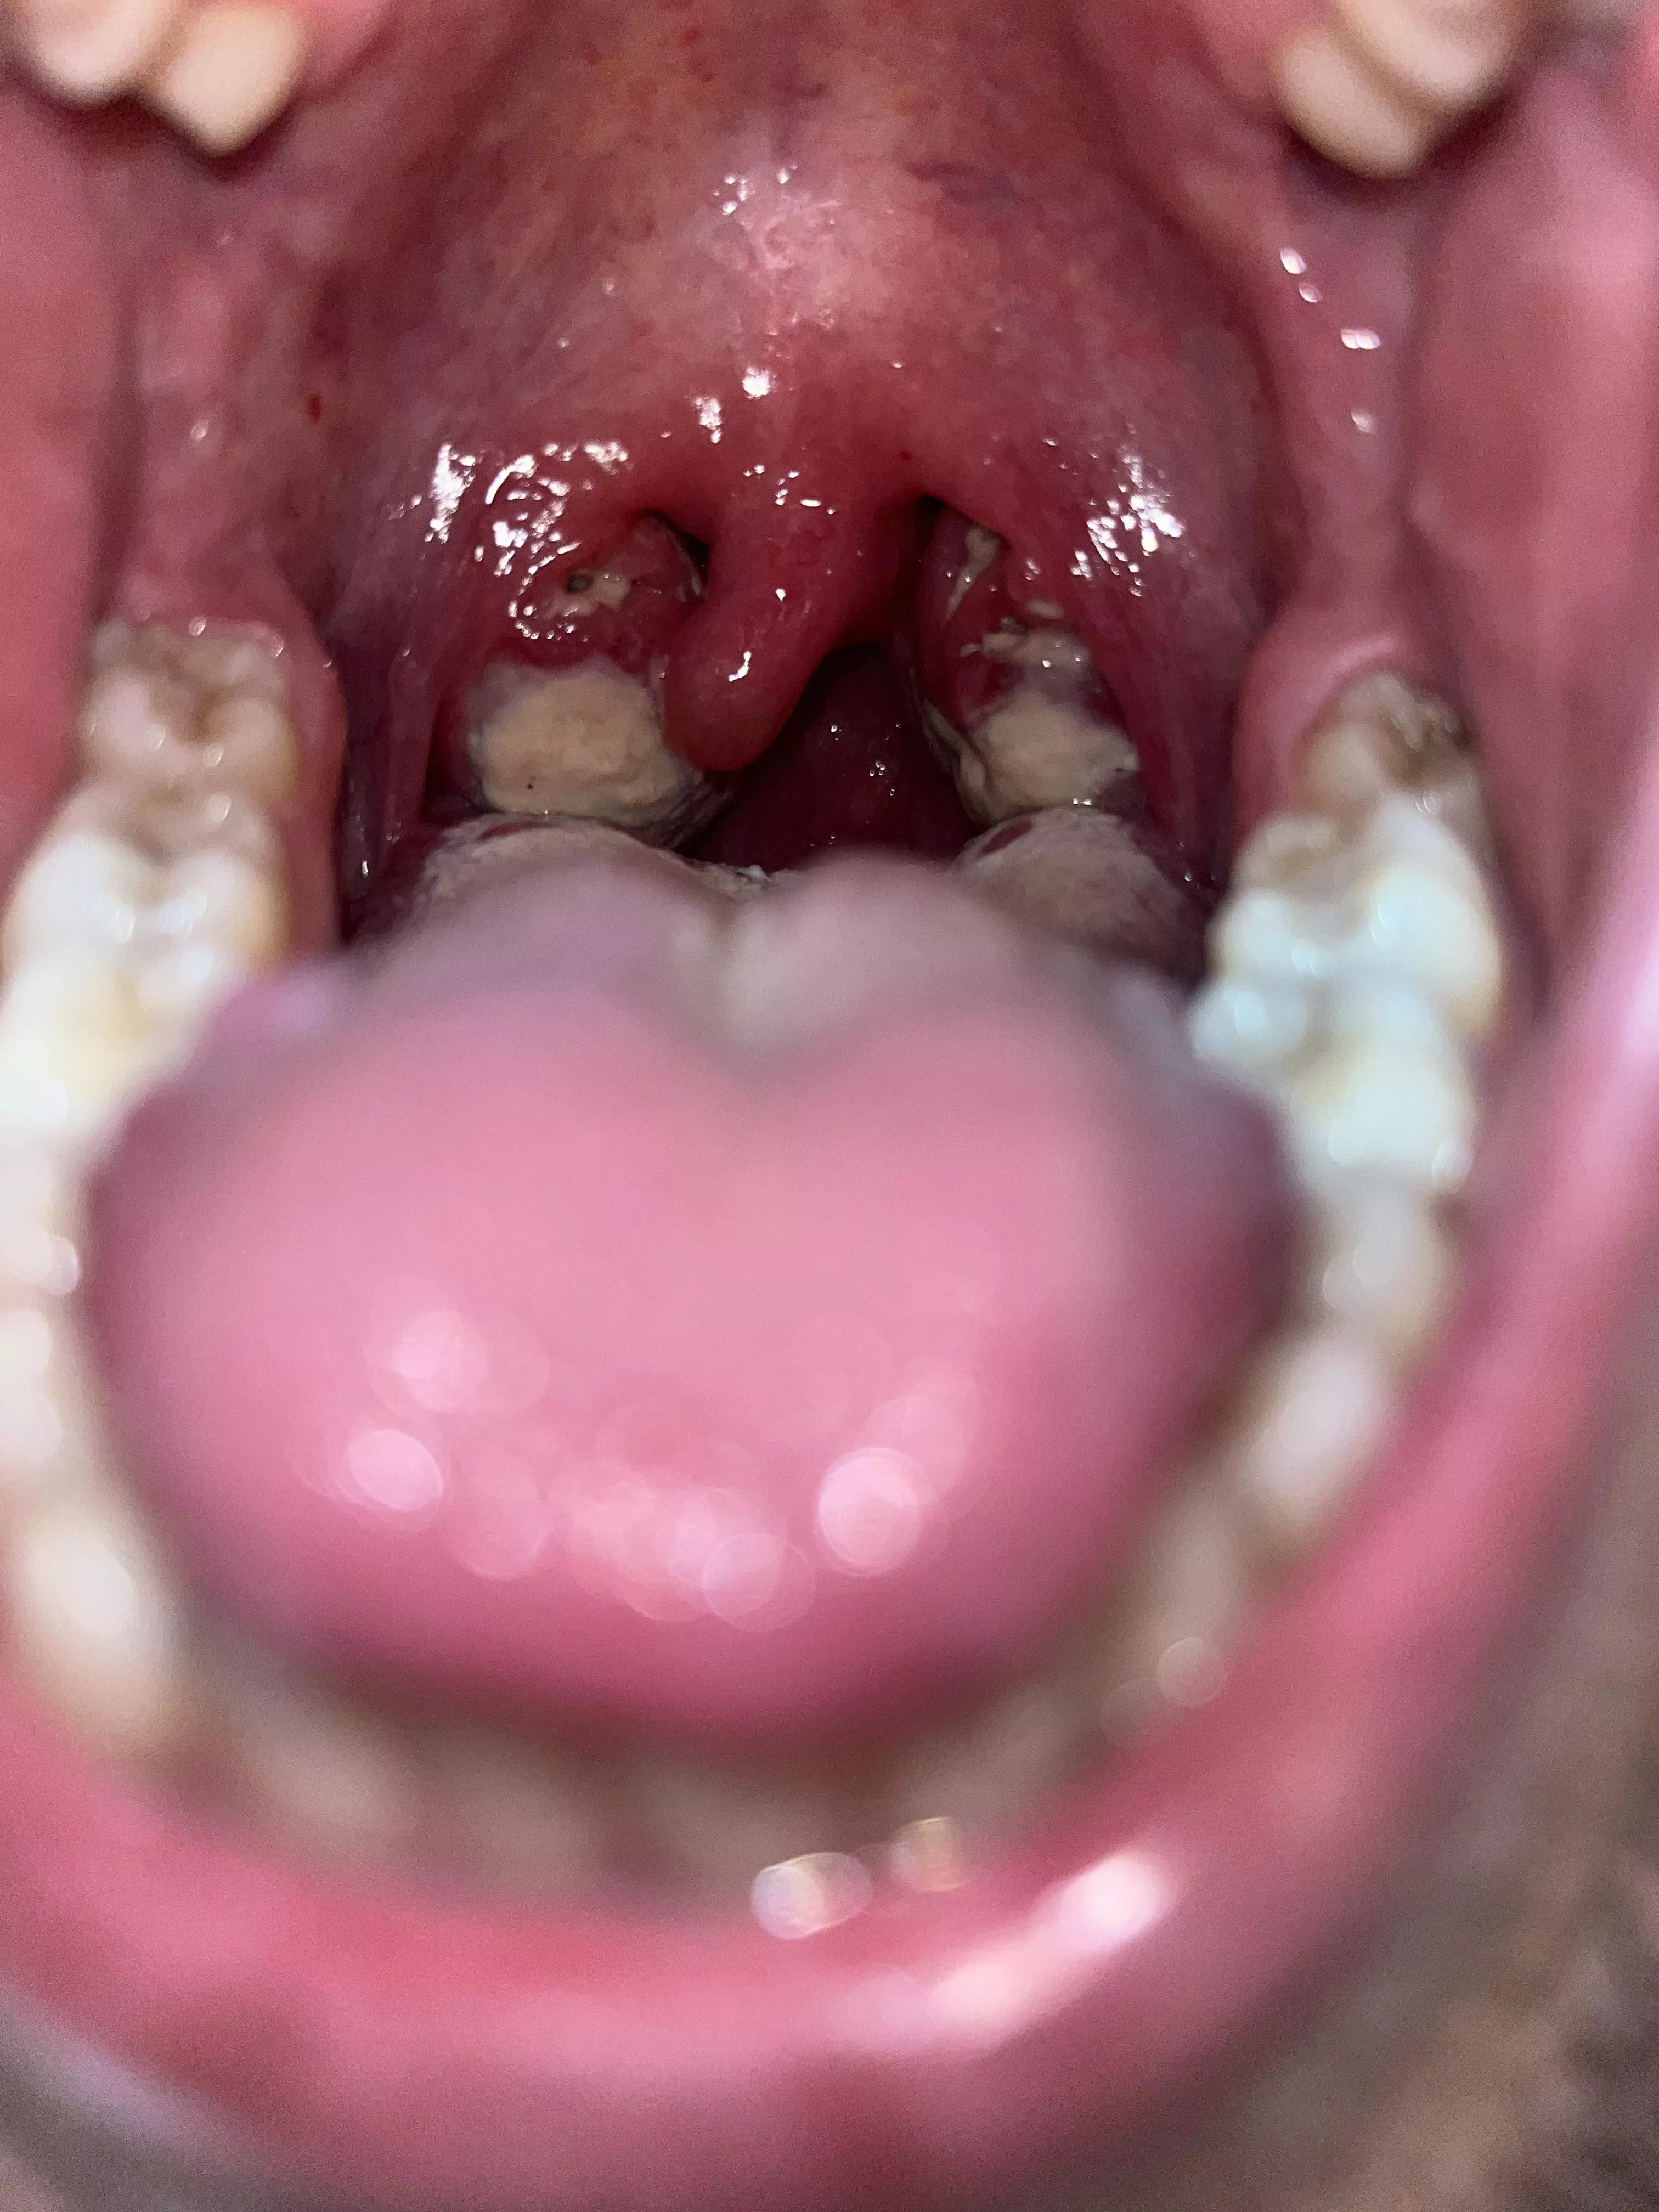

Infected with Mono and tonsillitis ๐ worst pain

Category: popping